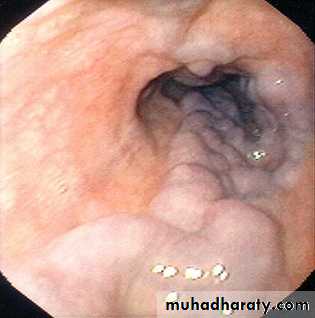

Esophagial Varices

VARICES• THREE common areas of portal/caval anastomoses

• 100% related to portal hypertension

• Found in 90% of cirrhotics

• MASSIVE, SUDDEN, FATAL hemorrhage is the most feared consequence